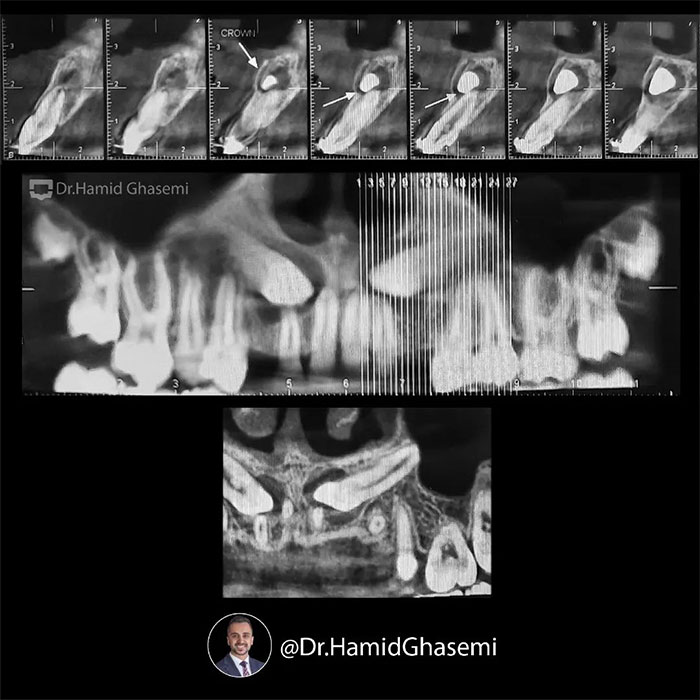

یک کیس خیلی جالب با مشکل جلوزدگی متوسط فک بالا و پایین (Bimaxillary dentoalveolar protrusion ) همراه با نهفتگی دوطرفه دندانهای نیش فک بالا. درمان با کشیدن دندان های نیش نهفته فک بالا و دندانهای پرمولر اول پایین انجام شد. تغییرات مثبت و قابل توجه در پروفایل و حالت لبهای بیمار پس از درمان و کسب اکلوژن کلاس ۱ ایده آل همچنان که دندانهای پرمولر اول بالا جایگزین دندانهای نیش نهفته در فک بالا شدند کاملا مشهود است.

This was such an amazing case with moderate bimaxillary dentoalveolar protrusion plus impacted bilateral upper canines. The case was treated by extraction of upper impacted canines and lower 1st premolars. Significant profile change achieved while upper 1st premolars substituted for upper canines properly with a solid perfect class 1 dental occlusion.